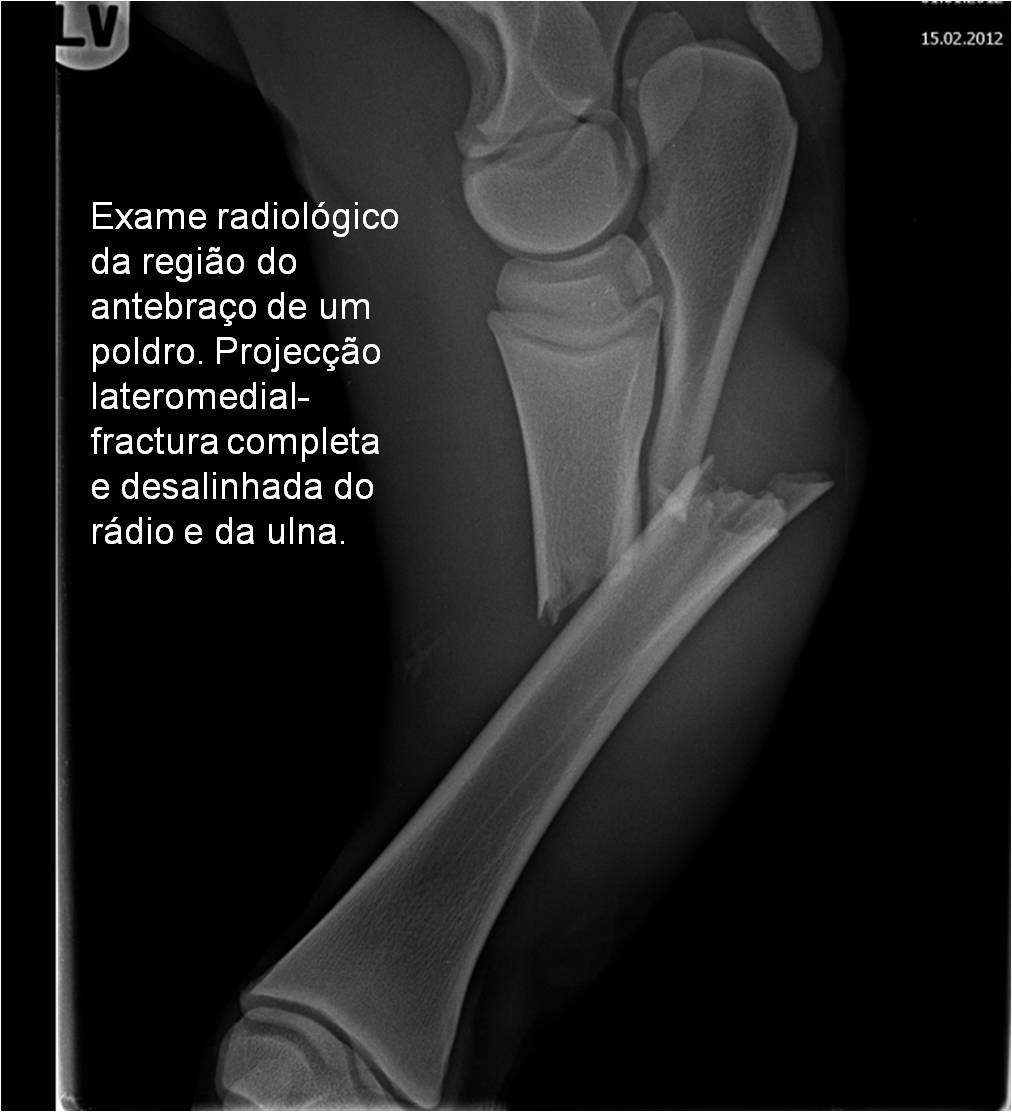

Publisher: Universidade de Évora

Abstract: O relatório de estágio encontra-se estruturado em três partes distintas. A primeira parte faz a caracterização das infraestruturas e funcionamento do Hospital Veterinário de Equinos de Lüsche, Oldenburg, Alemanha, assim como a análise casuística dos casos clínicos acompanhados durante os 6 meses de estágio. A segunda parte consiste de uma revisão bibliográfica sobre quistos do osso subcondral em equinos. Por fim, a terceira parte consta da apresentação e discussão de um caso clínico, nomeadamente o diagnóstico e acompanhamento imagiológico, por ressonância magnética, de um quisto subcondral na terceira falange num cavalo adulto; ### Abstract Equine Practice- Subcondral bone cyst of the third phalanx This internship report is divided in three parts. The first part characterizes the infrastructure and function of the Equine Hospital Lüsche, Oldenburg, Germany, as well as the casuistic of the clinical cases accompanied during the 6 month internship. The second part consists in a bibliographic review of cystic lesions of the subchondral bone in equines. The third part consists in a case report, the diagnostic and imagiological accompaniment, by use of magnetic resonance imaging, of a subchondral bone cyst in the distal phalanx of an adult equine.